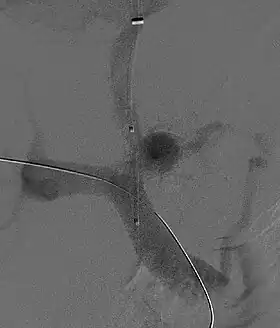

Portosystemic shunts

Selective shunts select non-intestinal flow to be shunted to the systemic venous drainage while leaving the intestinal venous drainage to continue to pass through the liver. The most well known of this type is the splenorenal.[16] This connects the splenic vein to the left renal vein thus reducing portal system pressure while minimizing any encephalopathy. In an H-shunt, which could be mesocaval (from the superior mesenteric vein to the inferior vena cava) or could be, portocaval (from the portal vein to the inferior vena cava) a graft, either synthetic or the preferred vein harvested from elsewhere on the patient's body, is connected between the superior mesenteric vein and the inferior vena cava. The size of this shunt will determine how selective it is.[17][18]

With the advent of transjugular intrahepatic portosystemic shunting (TIPS), portosystemic shunts are less performed. TIPS has the advantage of being easier to perform and doesn't disrupt the liver's vascularity.[19]